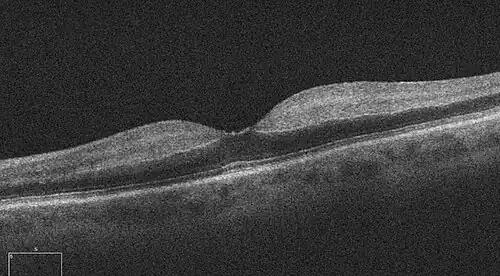

One diagnostic method for the confirmation of CRAO is fluorescein angiography, used to examine the retinal artery filling time after the fluorescein dye is injected into the peripheral venous system.[2] In an eye with CRAO some branches of the retinal artery may not fill or the time it takes for the branches of the retinal artery to fill will be increased, which is visualized by the leading edge of the fluorescein moving slower than normal through the retinal artery branches to the edges of the retina.[2] Fluorescein angiography can also be used to determine the extent of the occlusion as well as classify it into one of four types non-arteritic CRAO, non-arteritic CRAO with cilioretinal artery sparing, transient non-arteritic CRAO and arteritic CRAO.[3] Optical coherence tomography (OCT) may also be used to confirm the diagnosis of CRAO.[4]